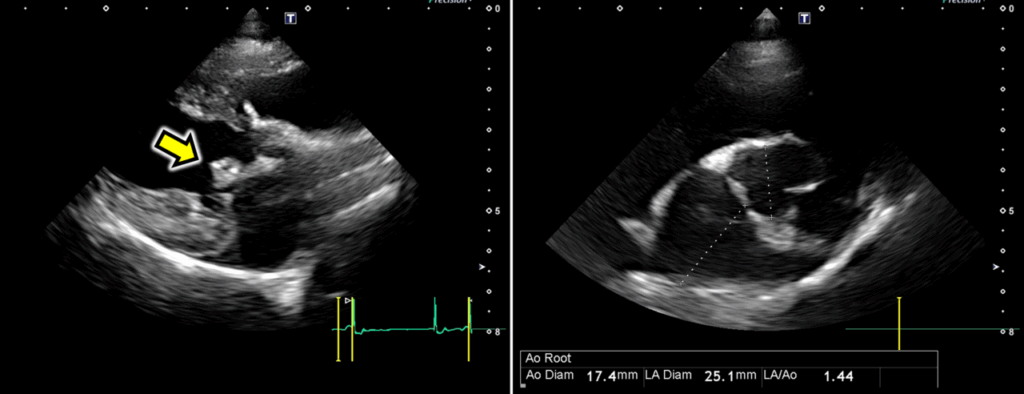

• 心エコー図検査(図2)

僧帽弁逆流が確認されましたが、左心房拡大はみられませんでした。

また、Mモード検査においてもLVIDDNは1.59であり、左心室拡大はみられませんでした。

これらのことから心不全や肺疾患ではなく、上部気道閉塞が呼吸器症状の原因であると考えました。